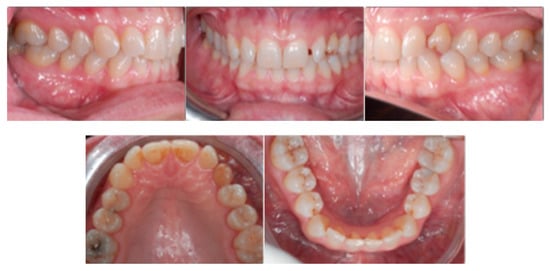

An adult female patient, 43 years old, with Class I occlusion on both sides and with a slight deep bite, light crowding, a persistent deciduous canine no. 63, and a horizontally impacted canine with the crown tip close to the lateral incisors and the tip of the root protruding beyond the buccal bone in the 2.3 area is presented in Figure 9 and Figure 10.

Class I occlusion on both sides with a slight deep bite, light crowding, a persistent deciduous canine no. 63, and a horizontally impacted canine with the tip of the crown close to the lateral incisors and the tip of the root protruding beyond the buccal bone in the 2.3 area.

Figure 10.

CBCT pictures of the patient. Since the patient was subjected to periodic radiographic control as she was a cancer survivor, the decision was to do a CBCT to receive all the informations useful for the deimpaction treatment and avoid conventional orthodontic X-rays like panoramic and lateral X-rays.